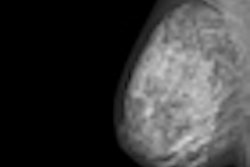

We often hear about how some women experience pain while undergoing mammography screening, and this may be a reason why women don't return for a follow-up or repeat examination. Have you ever wondered how many patients really feel pain? And what percentage of women miss their examinations because it's too painful? Research presented at the European Congress of Radiology (ECR) tries to answer these questions. Click here for our report.

In other news, healthcare professionals are always on the lookout for ways to improve breast cancer screening. A new study in European Radiology finds diffusion-weighted MRI may be a promising tool for the future. Find out why.

How much does CAD aid radiologists doing initial breast cancer reads? You might be surprised how much it can affect your workload. Read about research from Israel that was presented at ECR 2012.